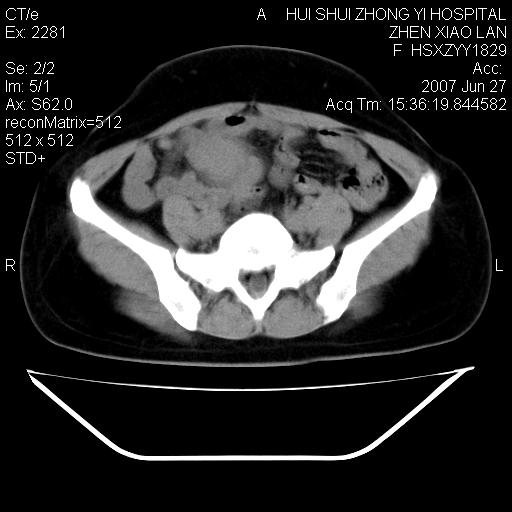

以下是引用还珠格格在2007-6-28 15:15:00的发言:[br]子宫明显增大,偏向盆腔右侧,密度均匀,和子宫同密度, 考虑 子宫肌瘤可能性大 建议增强 除外子宫平滑肌肉瘤。

以下是引用dyqct在2007-6-28 15:41:00的发言:[br]考虑多发子宫肌瘤可能性大,建议进一步增强检查。